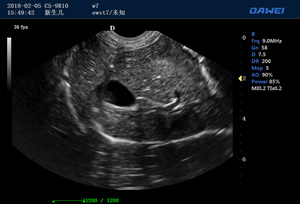

·支持B、C、PW、CW、寬景成像